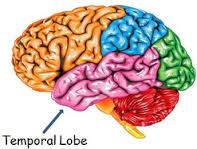

Temporal Lobes

This region of the brain is comprised of the primary auditory cortex and areas of the brain involved in the comprehension and production of spoken language (speech center of the brain). They are also responsible for memory development and learning. The temporal lobes are associated with several behaviors and functions of the human brain that include processing of auditory input; comprehension of spoken language; language production (choosing the appropriate words and fluency of spoken speech); and verbal and visual memory.

This region of the brain is comprised of the primary auditory cortex and areas of the brain involved in the comprehension and production of spoken language (speech center of the brain). They are also responsible for memory development and learning. The temporal lobes are associated with several behaviors and functions of the human brain that include processing of auditory input; comprehension of spoken language; language production (choosing the appropriate words and fluency of spoken speech); and verbal and visual memory.